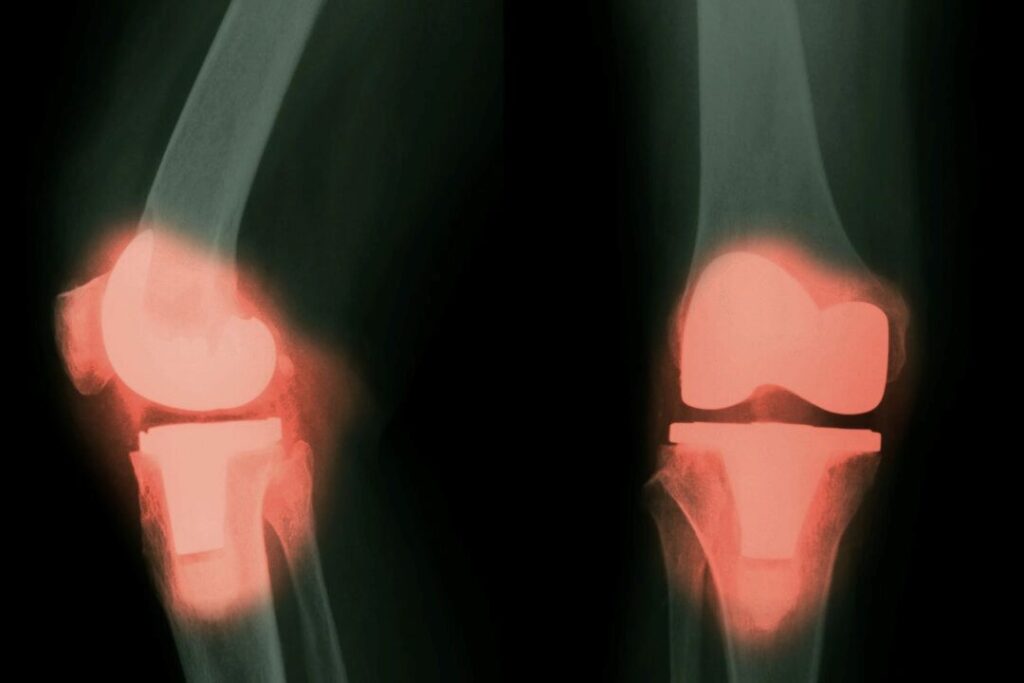

人工関節からの金属が血液と脳に入る可能性=研究

新たな研究によると、大型関節の置換手術を受けた患者は、血液、脳、脊髄液中の一部の金属濃度が上昇し、長期的に神経に悪影響を及ぼす可能性があることが明らかになりました。

アメリカでは、年間約79万件の膝関節全置換術と54万4千件の股関節置換術が行われており、高齢化の進展によりこの件数は今後さらに増加すると予想されています。